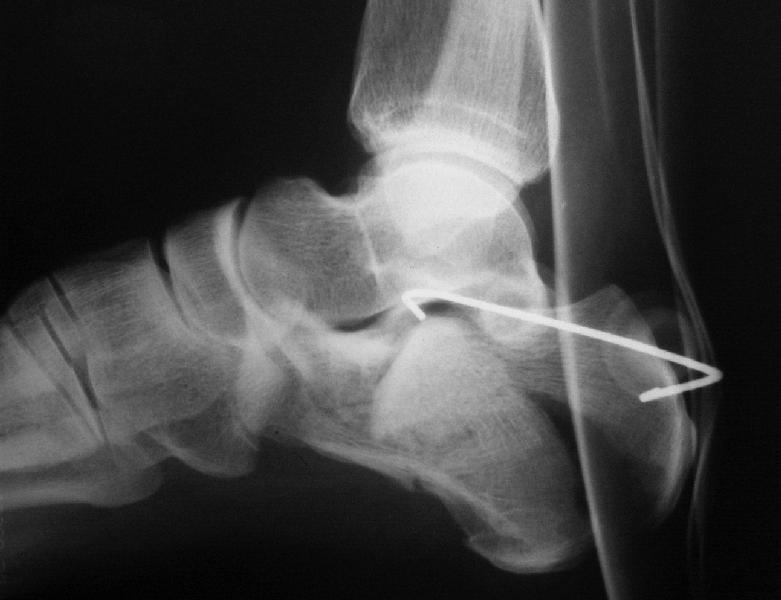

Кроме стандартных снимков, необходим контроль конгруэнтности суставной поверхности (проекции Бродена)